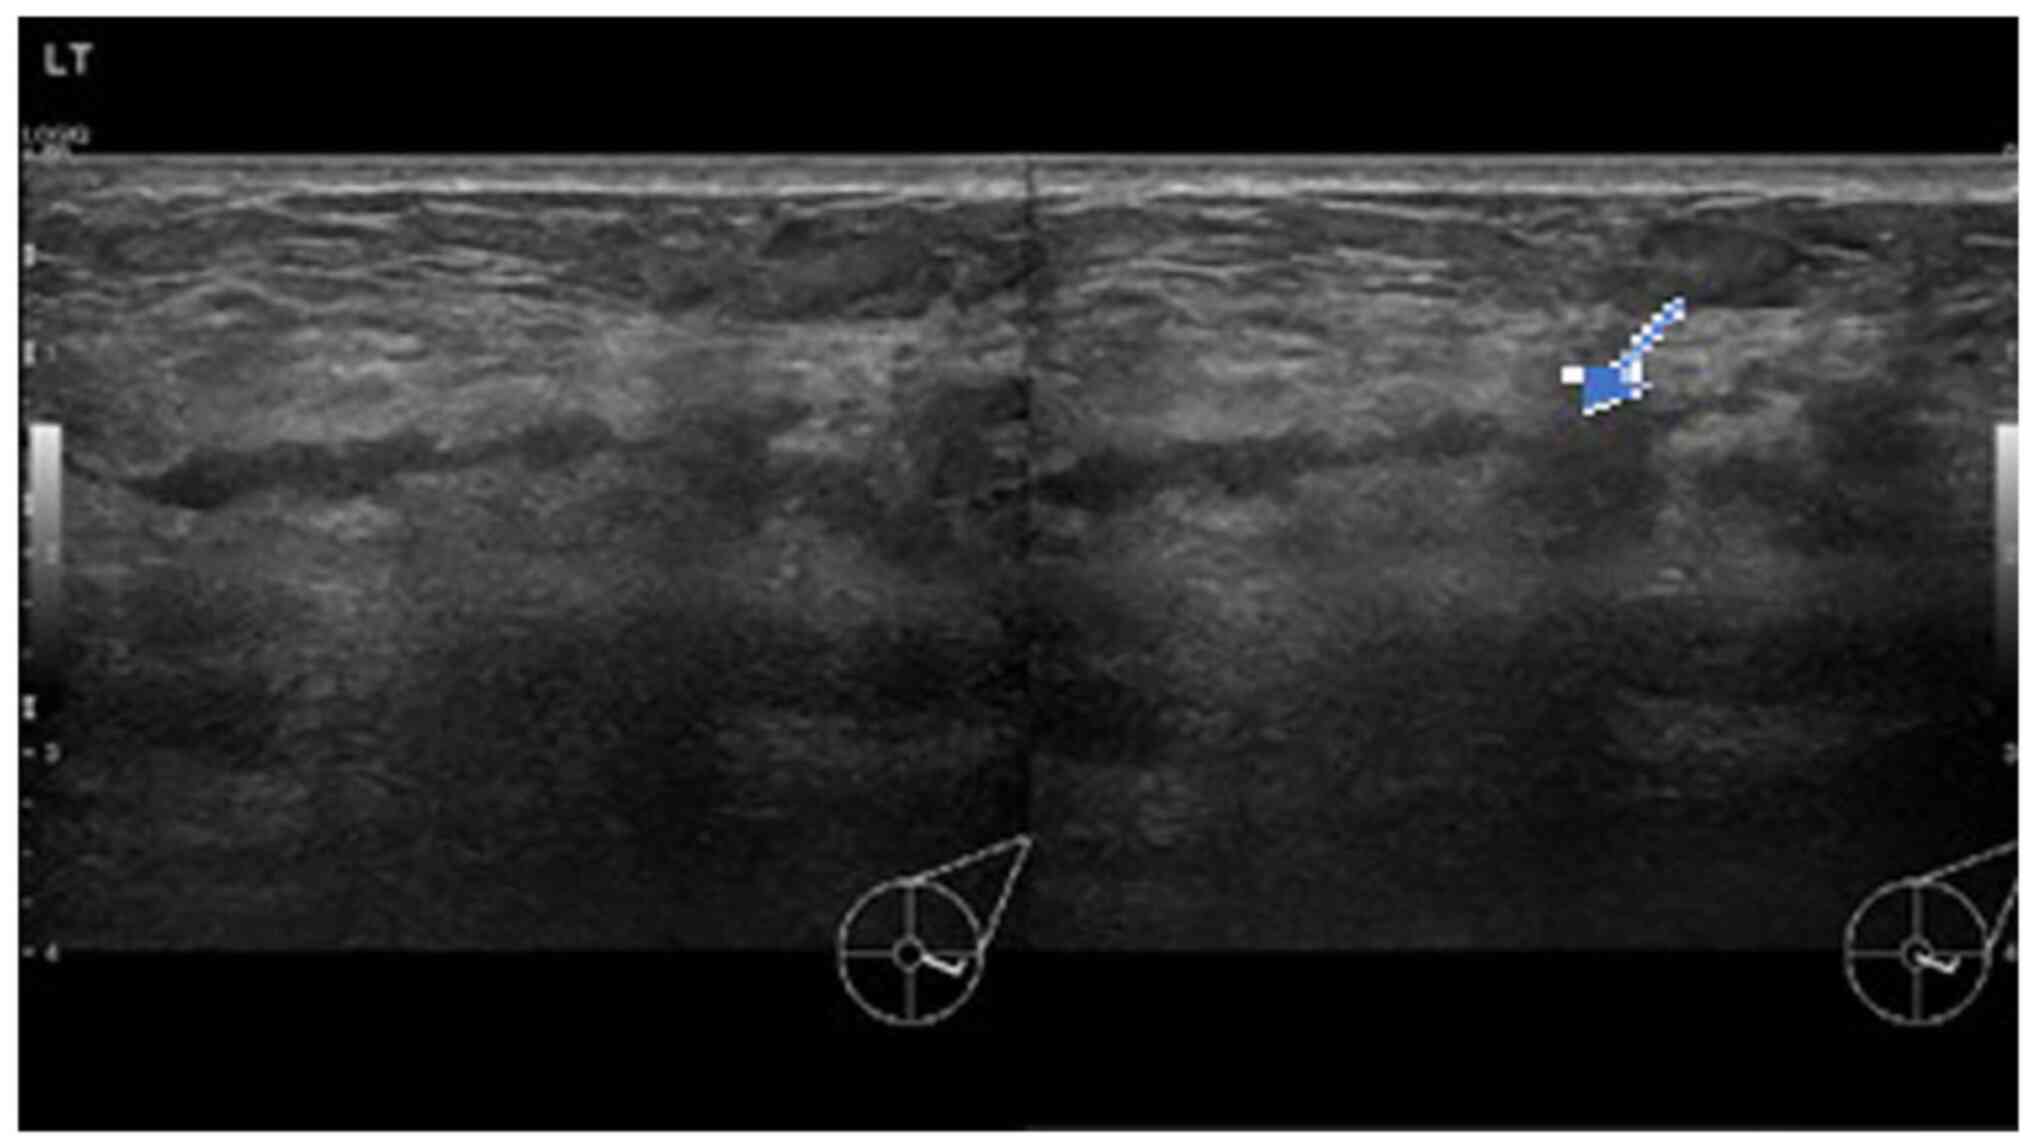

In view of the persistence of the mass, a breast ultrasound was performed. The initial examination yielded normal results. A second ultrasound repeated after 10 days (Fig. 1) revealed an area of architectural distortion with dilated ducts measuring up to 0.3 cm in diameter located at the 3 to 4 o'clock position of the left breast. There was no discrete mass or significant axillary lymphadenopathy. The findings were consistent with mastitis. The other differential diagnosis was inflammatory breast carcinoma. The patient was treated with a course of oral Augmentin (amoxicillin and clavulanic acid) and although the swelling decreased in size, it did not completely resolve. A third ultrasound (Fig. 2) after 2 weeks of treatment was suggestive of a 1.3-cm hypoechoic mass with indistinct borders at the 4 0'clock position. A decision was made to proceed with a biopsy. A repeat ultrasound (Fig. 3) was conducted after 6 months, which revealed hypoechoic tubular collections and fistulous tracts towards the skin.

Figure 1

Ultrasound images illustrating transverse (right panel) and longitudinal (left panel) views of architectural distortion and dilated ducts 10 days after the initial presentation with a breast lump and pain. The arrow indicates a dilated duct surrounded by a wide area of architectural distortion.